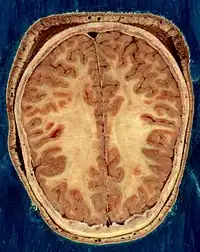

![]() Cerebro humano en rojo. | ||

- ↑ Del Proyecto "Humano Visible" (Visible Human Project de la Biblioteca Nacional de Medicina de Estados Unidos. En este proyecto, dos cadáveres humanos (de un hombre y una mujer) fueron congelados y luego cortados en láminas delgadas, que fueron fotografiadas y digitalizadas individualmente. Esta sección está tomada a una pequeña distancia de la parte superior del cerebro, y muestra la corteza cerebral (la capa celular plegada al exterior) y la sustancia blanca subyacente, que consiste en tramos de fibra mielinizada que viaja hacia y desde la corteza cerebral.